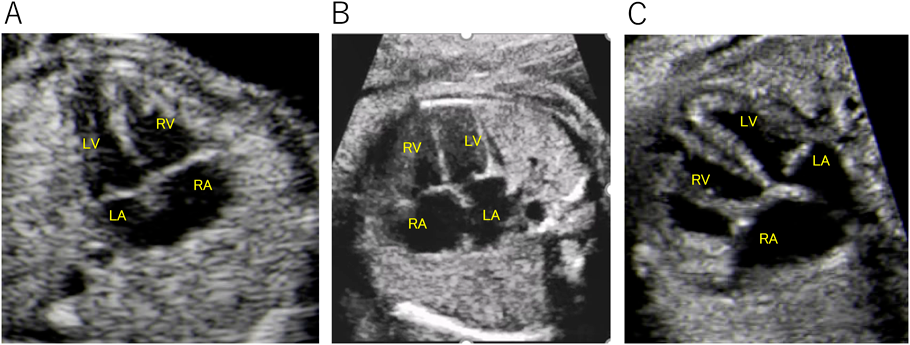

まず,CHDの種類について言及しなければならない.ここでは重症度の判断ではなく,スクリーニング/診断について述べる.2020年の多施設共同研究では,左心低形成症候群や単心室の診断率は60~70%程度であるのに対し,完全大血管転位は50%に満たない数字であり,単独の総肺静脈還流異常は20%程度である12).無論これらの数値は各施設や報告で異なるわけだが,胎児診断率の高い順に疾患を並べると,どの報告もほぼ同じになる.4-chamber viewでの異常,特に心室の大きさや数に異常を来す疾患は診断率が高いと言える.純型肺動脈閉鎖は比較的高い診断率を示しているが,右心室の容量によってはスクリーニングでの抽出率に影響が出るであろう.一方で,完全大血管転位やファロー四徴症は4-chamber viewで異常を呈することが少なく,3-vessel viewやoutflow-tract viewまで確認しなければ診断に至ることは難しい.つまり,4-chamber viewがきれいに描出できたから大丈夫というのが落とし穴となりうる.大動脈縮窄をどの程度胎児診断できるのかは,小児循環器医としては興味のあるところであるが,大動脈縮窄単独では,前述の多施設協同研究でも3割程度の診断率であり,いくつかのパラメーターを組み合わせなければ診断に至れないCHDの一つと言える.Fig. 1に3疾患の4-chamber viewを載せたが,このviewのみでどれだけ診断に迫れるだろうか.

Pediatric Cardiology and Cardiac Surgery 37(4): 265-276 (2021)

Fig. 1 4-chamber view of congenital heart disease

A: Tetralogy of Fallot. B: Transposition of the great arteries. C: Coarctation of the aorta. LA, left atrium; LV, left ventricle; RA, right atrium; RV, right ventricle.